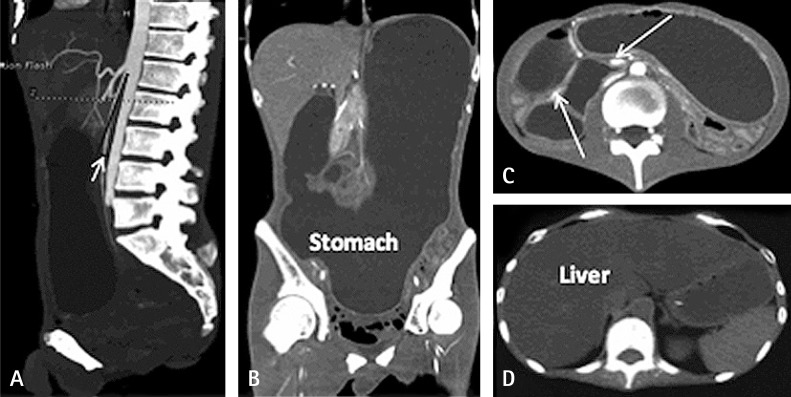

Table 1

Biochemical test results and nutrition therapy of the patient

Hospital Stay, days -7 -1 1 8 12 16 22

TG, mmol/L 18.08 4.88 15.61 15.17 11.09

ALT, U/L 78 46 50 44 47 41 15

Hemoglobin, g/L 77 74 80 113 97 74

Total energy per day, kcal 1612 1283 1179 1400 1800 1710 1610

NPC, kcal 1432 1147 1043 1220 1620 1550 1450

Fat, g 68 51 51 68 68 50 50

Fat, g/kg 1.94 1.46 1.46 1.94 1.94 1.43 1.43

Glucose, g 205 172 147 130 230 275 225

Glucose, g/kg 5.86 4.06 4.2 3.71 6.57 7.86 6.43

Amino acids, g 45 34 34 45 45 40 40

Amino acids, g/kg 1.29 0.97 0.97 1.29 1.29 1.14 1.14

Proportion of energy supply by glucose, % 57 60 56 43 57 71 62

Proportion of energy supply by fat, % 43 40 46 57 43 29 38

TG: triglyceride, ALT: alanine aminotransferase, NPC: daily intake of non-protein calories, Fat (g/kg): grams of fat intake per kilogram of body weight, Glucose (g/kg): grams of glucose intake per kilogram of body weight, Amino acids (g/kg): grams of amino acids intake per kilogram of body weight.

Table 1 Biochemical test results and nutrition therapy of the patient